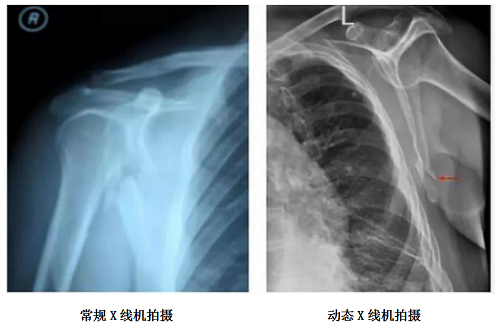

动态dr在复杂体位摄片中的精准高效优势